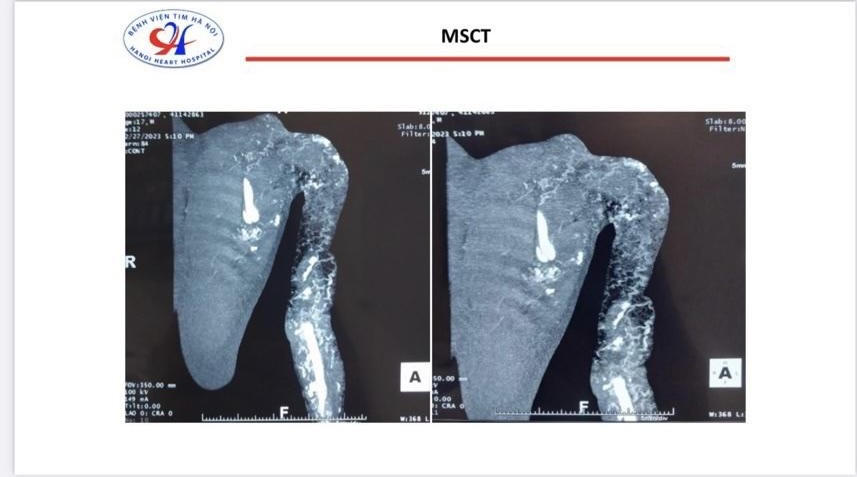

Hình ảnh phim chụp cho thấy cánh tay trái của bệnh nhân rỗ như tổ ong. Ảnh: BVCC |

PGS.TS Nguyễn Sinh Hiền, Giám đốc Bệnh viện Tim Hà Nội cho biết, đây là một ca bệnh phức tạp. Trước đó, bệnh nhân đã đi khám nhiều nơi nhưng không tìm ra bệnh. Kết quả chụp cắt lớp điện toán đa lát cắt cho thấy cánh tay trái của bệnh nhân rỗ như tổ ong. Bệnh nhân bị hạn chế hoạt động, tay trái yếu, bị chèn ép thần kinh.